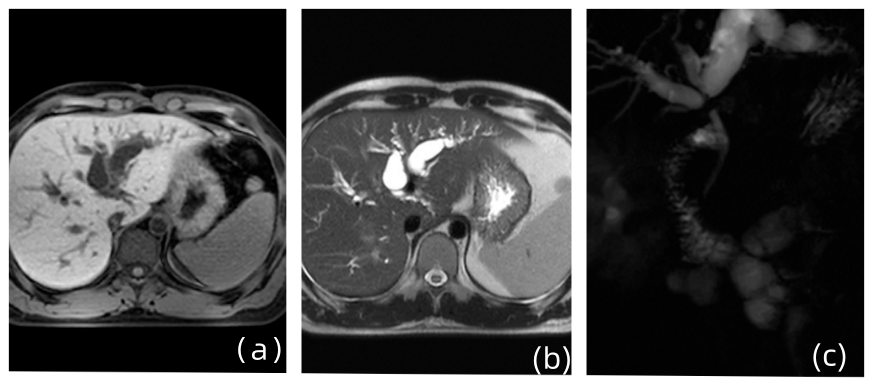

- 1型自身免疫性胰腺炎的药物治疗 1型自身免疫性胰腺炎是一种以胰腺慢性炎症和纤维化为主要特征的慢性炎症性疾病,经典治疗手段如糖皮质激素、单克隆抗体及免疫调节剂在自身免疫性胰腺炎诱导治疗和维持治疗中起到关键作用……